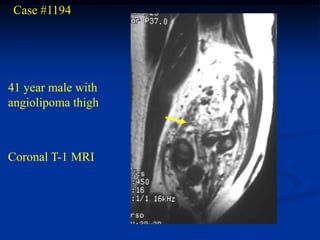

Case #1194

41 year male with

angiolipoma thigh

Coronal T-1 MRI

Axial T-1 MRI

Case #1194 41 yearmale with angiolipoma thigh Coronal T-1 MRI

• 98.